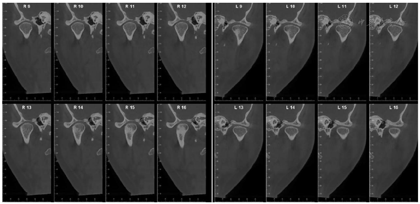

X线示37区于就诊前外院植入种植体(位置较差),15、16种植体联冠,全口牙牙槽骨吸收至根尖1/2~根尖1/3,尤以11、22、32牙槽骨吸收为甚。双侧颞下颌关节区骨皮质连续,形态不完全对称。安氏Ⅱ类+骨性Ⅱ类;低角水平生长型;牙周炎(重度);牙列拥挤合并牙列散隙及三角间隙;深覆盖Ⅲ°;

经过矫正前的牙周系统治疗以及22个月的矫正加稳定并联合矫治期间定期的牙周维护治疗,矫治结束后患者上下牙列牙齿排列整齐,建立了正常的覆牙合覆盖,维持了双侧磨牙、尖牙咬合关系,未有咬合干扰点,达到稳定的咬合关系。同时,牙周袋并未加深,11瘘管愈合(图2),全口牙龈颜色正常,牙周组织无活动性炎症出现,另外,患者口内治疗前多颗松动的牙齿,其松动度也有明显的改善,例如治疗前11、22松动Ⅲ°,23松动Ⅱ°,12、36~41松动Ⅰ°。治疗后11、22松动Ⅰ°,其余牙齿稳定无松动现象。X线表现(图9)治疗后牙槽骨吸收停止且23~26近远中,36远中以及27近中等部位均有少量牙槽骨再生,骨白线连续性亦有增加,下前牙区牙槽骨高度有少量增加。关节矢状面、冠状面保持稳定,FloridaProbe牙周检查最终探诊深度普遍降至1~3 mm。X线头影测量前后对比以及重叠图可见上前牙内收较明显,下切牙压低有效,侧貌突度明显改善(图10,图11,图12,图13,图14)。

1.研究表明牙周炎患者经牙周治疗2~6个月后,若达到菌斑控制良好、软硬组织无炎症且软硬组织厚度充足等条件,且经评估无正畸禁忌症时可行正畸治疗[6]。本病例经过规范的牙周基础治疗,并进行了下前牙的翻瓣手术,最终探诊深度普遍小于3 mm。从X片可见,牙槽骨吸收停止且23~26近远中、36远中以及27近中等部位均有少量牙槽骨再生,骨白线连续性亦有增加,下前牙区牙槽骨高度有少量增加,达到正畸治疗的准入标准。